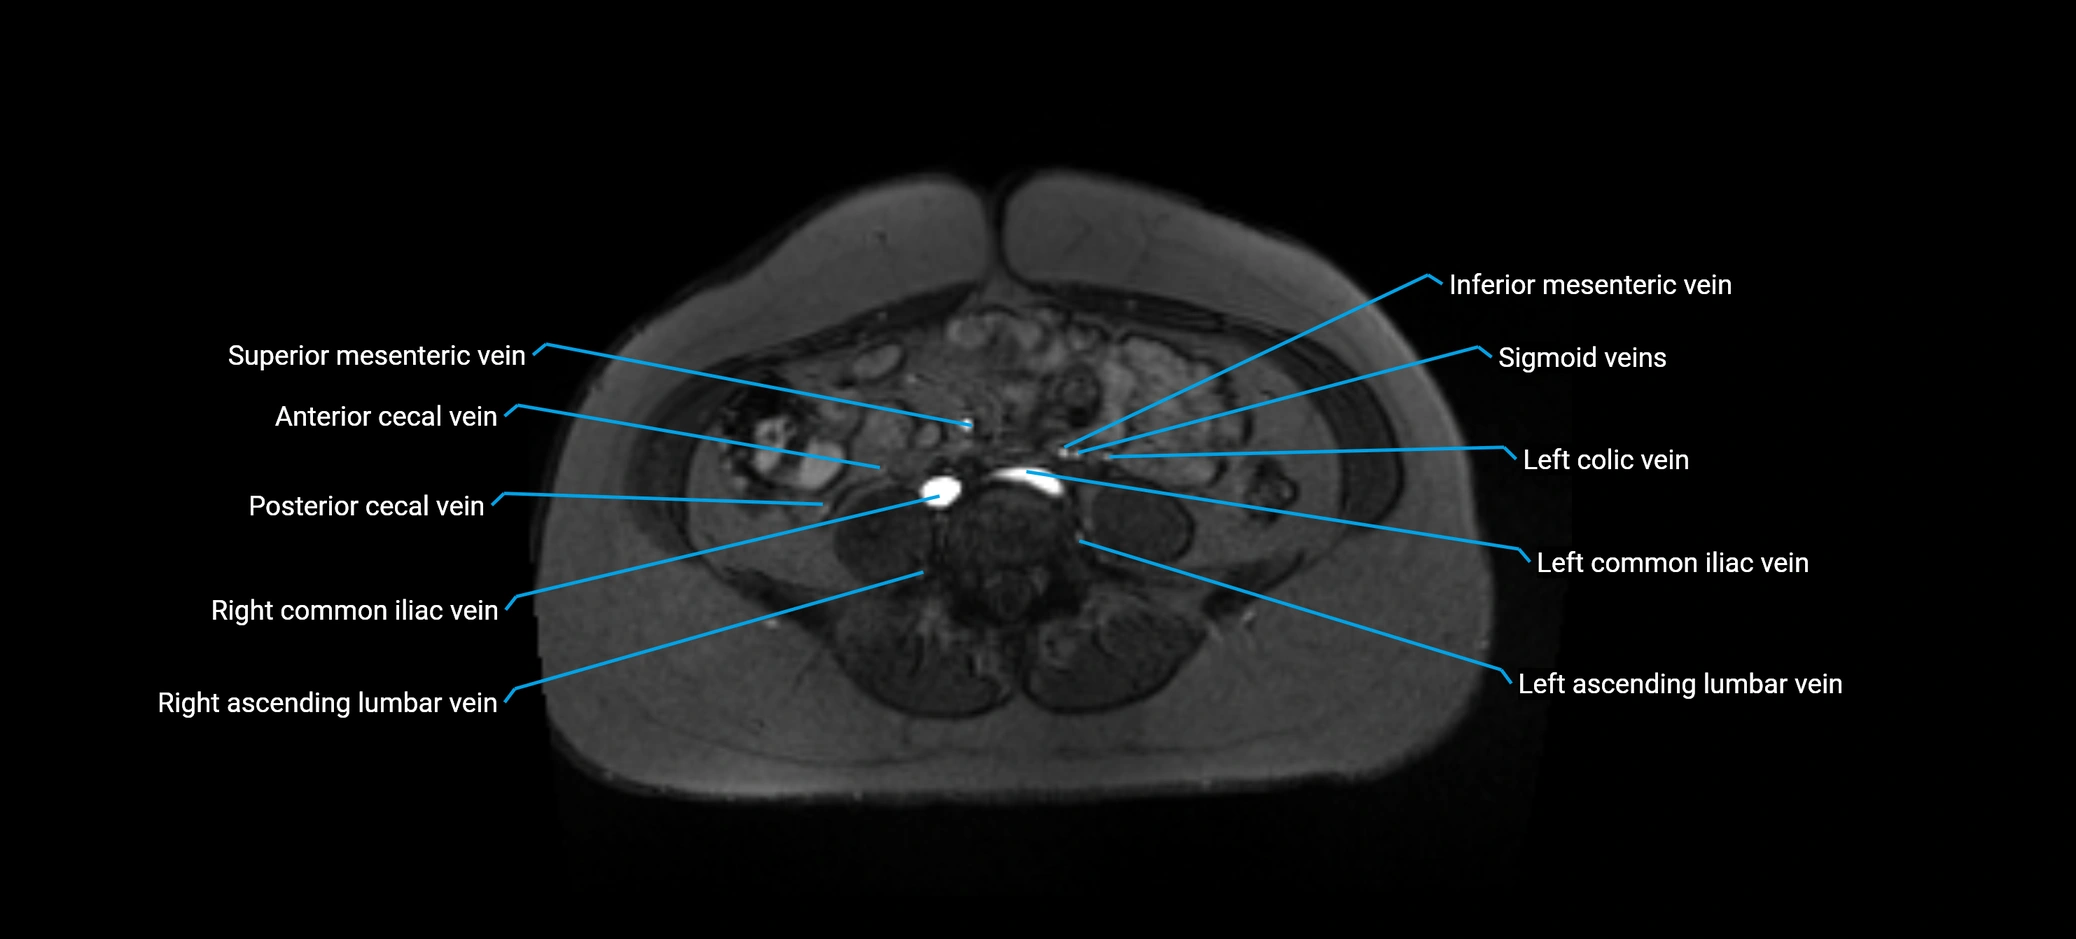

MRI image

image